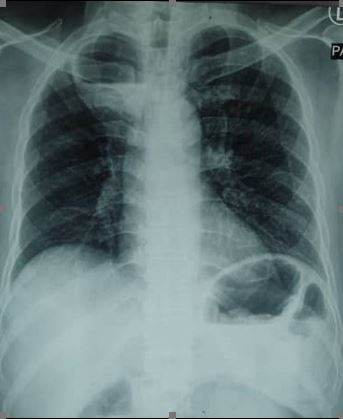

PICTORIAL